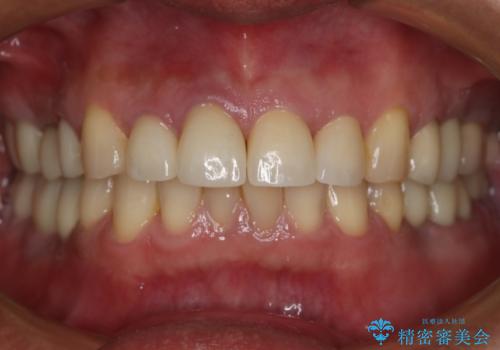

前歯の被せ物をリニューアル

- 上の前歯の正中離開と色味の不満を主訴にご来院されました。

神経を取っている右上2番目の歯は根尖部に病巣があったため根管治療をした上で土台を立て、被せ物の作製を行いました。右上1番目の歯は他院にてとても大きく深い金属の土台が入れられており被せ物の色調に影響を与えていましたが、すべて取りきることのリスクが高いため途中まで除去し目立ちにくいファイバーコアで補強と色調の改善を行いました。

- 税込¥627,000-費用は治療当時の料金となります